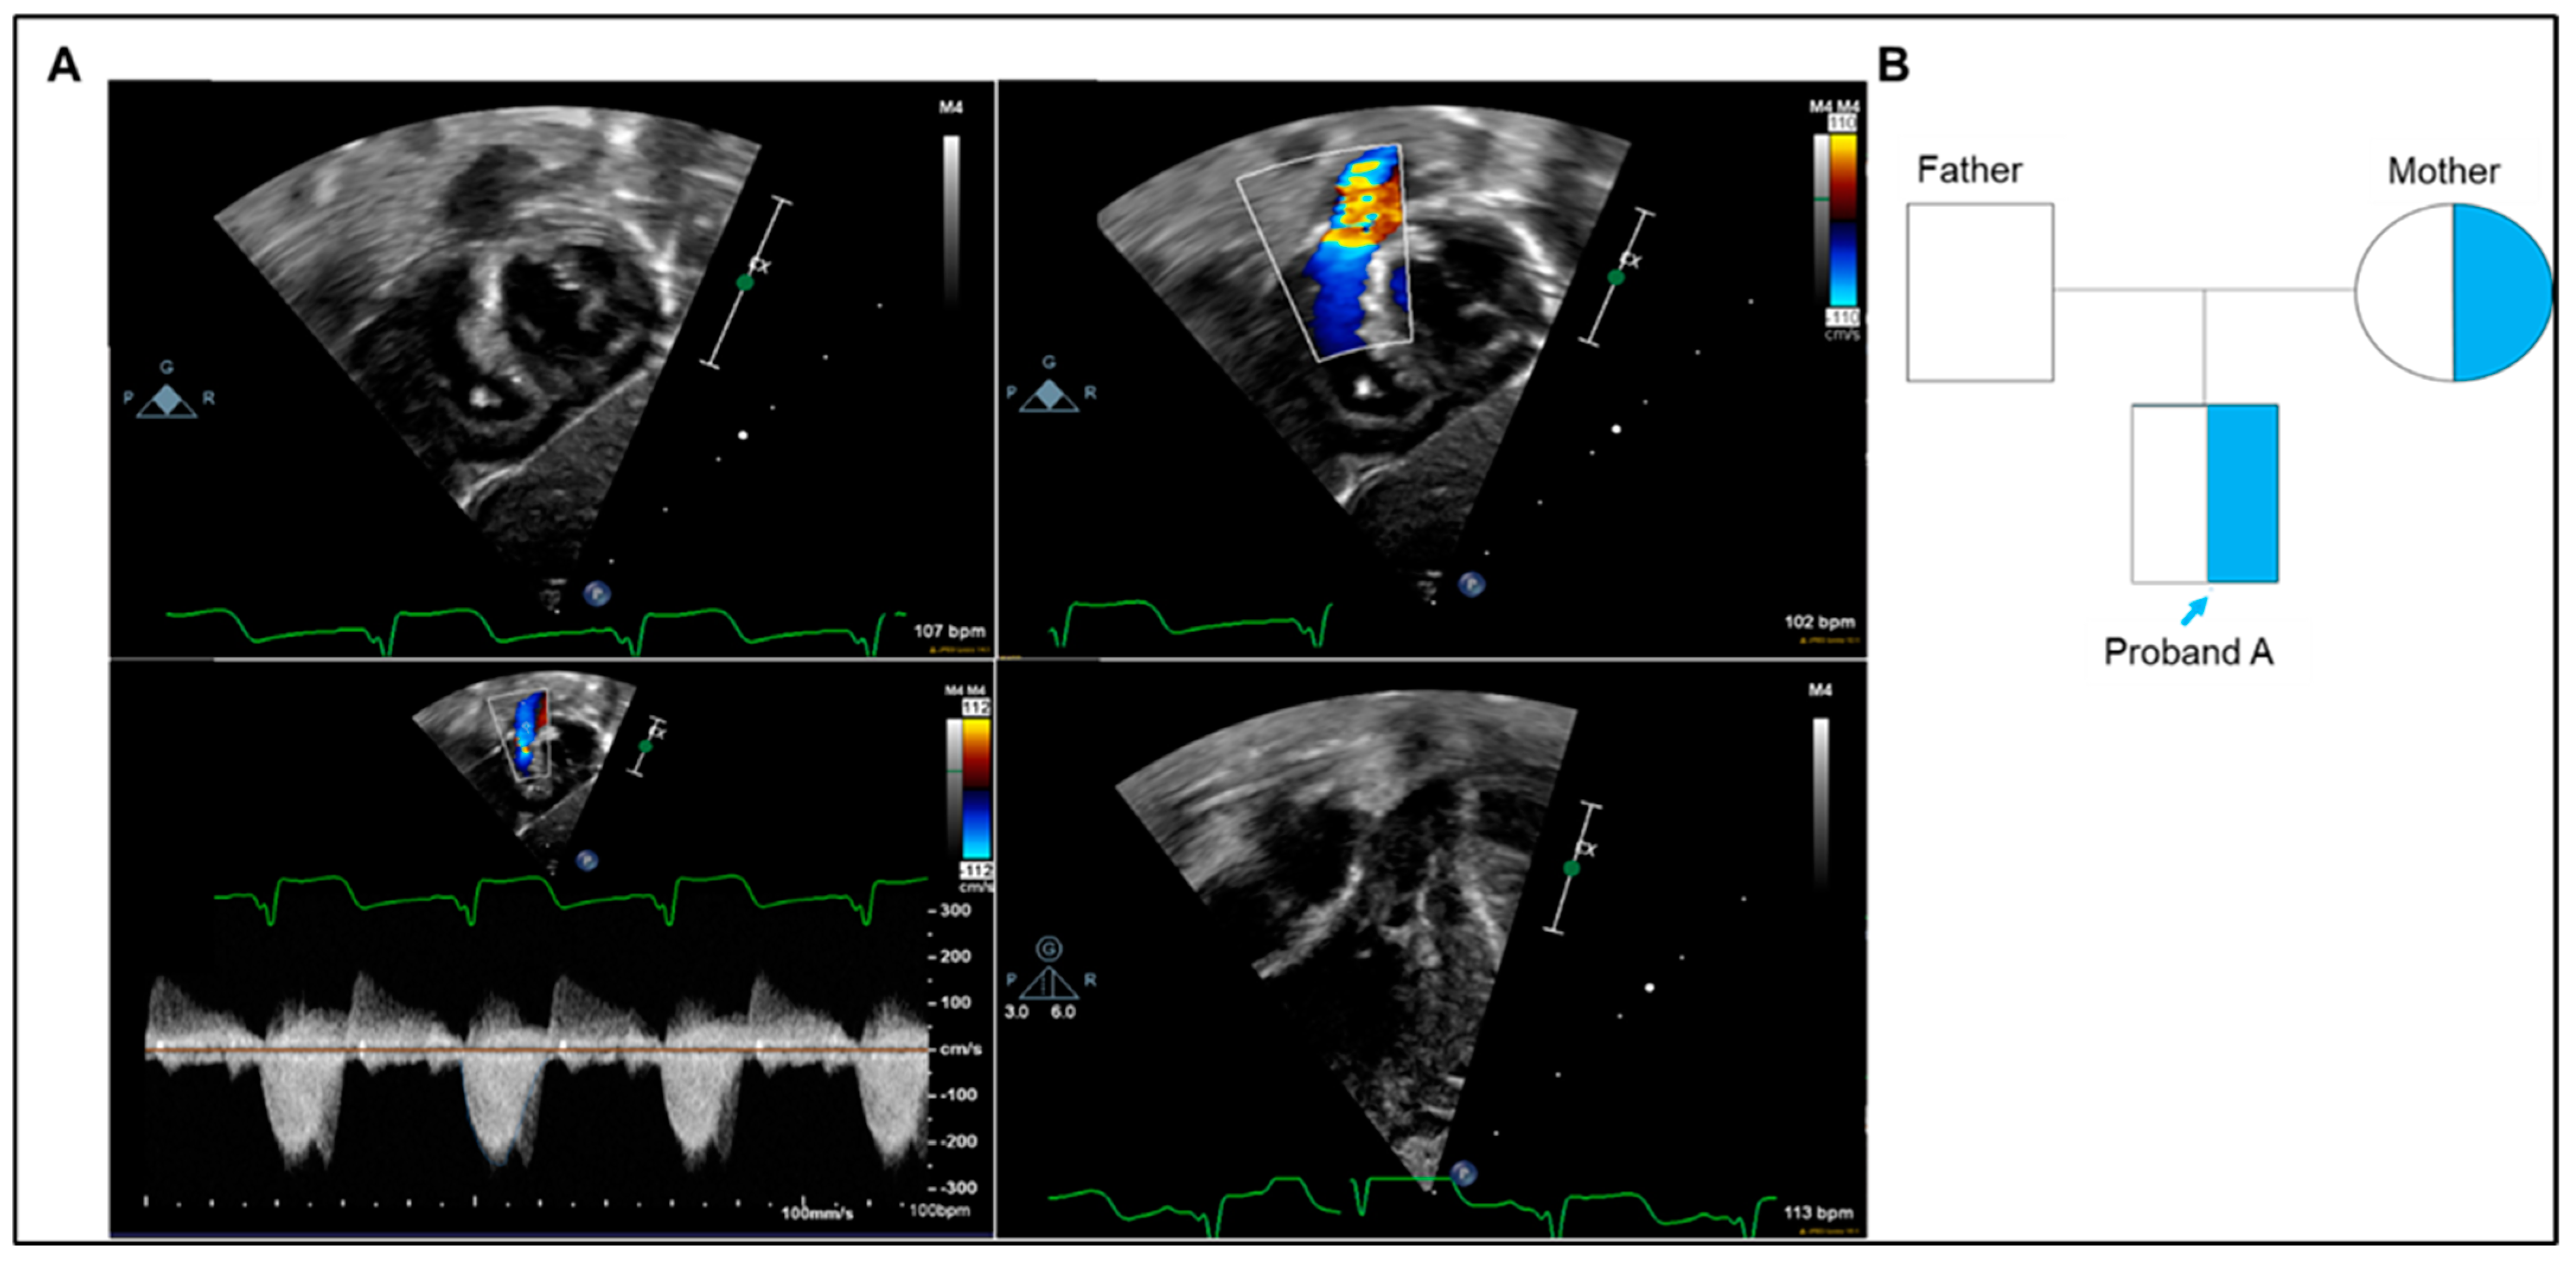

2.1.1. Case A

| GATA5 | Chr20:g.61041597C>G | c.710G>C | NM_080473.4 GRCh37/hg19 | p.Arg237Pro | VUS | Heterozygous | Mother (not in maternal uncle) |